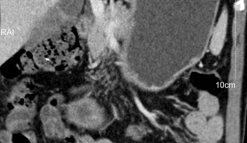

胃癌专科化CT检查及结构化报告